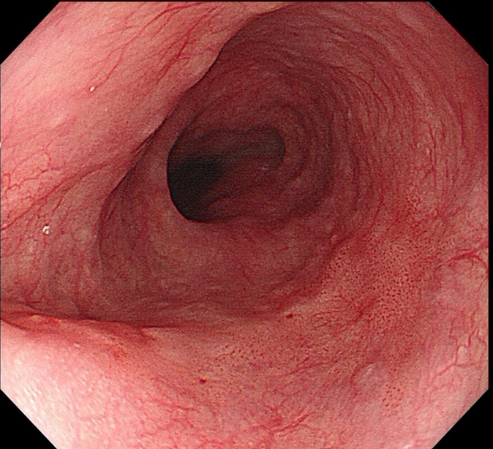

通过两个案例,一起直观地感受一下特殊内镜检查与普通胃肠镜有何差别

【早期食管癌】

【早期胃癌】